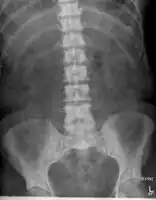

-

Sclerosis of the bones of the pelvis due to prostate cancer metastases

The most important distinction made by any staging system is whether the cancer is confined to the prostate. In the TNM system, clinical T1 and T2 cancers are found only in the prostate, while T3 and T4 cancers have metastasized. Several tests can be used to look for evidence of spread. Medical specialty professional organizations recommend against the use of PET scans, CT scans, or bone scans when a physician stages early prostate cancer with low risk for metastasis.[95] Those tests would be appropriate in cases such as when a CT scan evaluates spread within the pelvis, a bone scan looks for spread to the bones, and endorectal coil magnetic resonance imaging evaluates the prostatic capsule and the seminal vesicles. Bone scans should reveal osteoblastic appearance due to increased bone density in the areas of bone metastasis—the reverse of what is found in many other metastatic cancers.